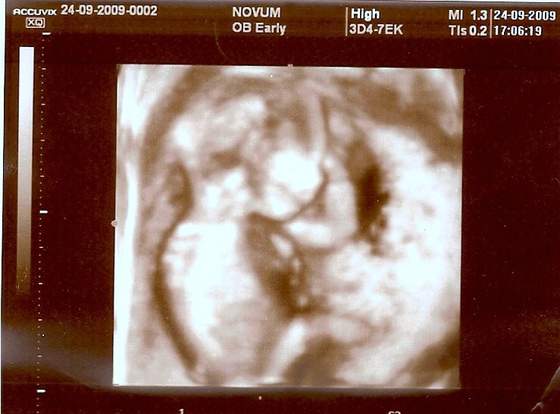

Tylko nie wiem czy to, co czuje to ruchy

Buziaczek dla kruszynki albo kruszynkaa to mój kruszynek)) albo kruszynka :-):-):-)

a to mój kruszynek)) albo kruszynka :-):-):-)